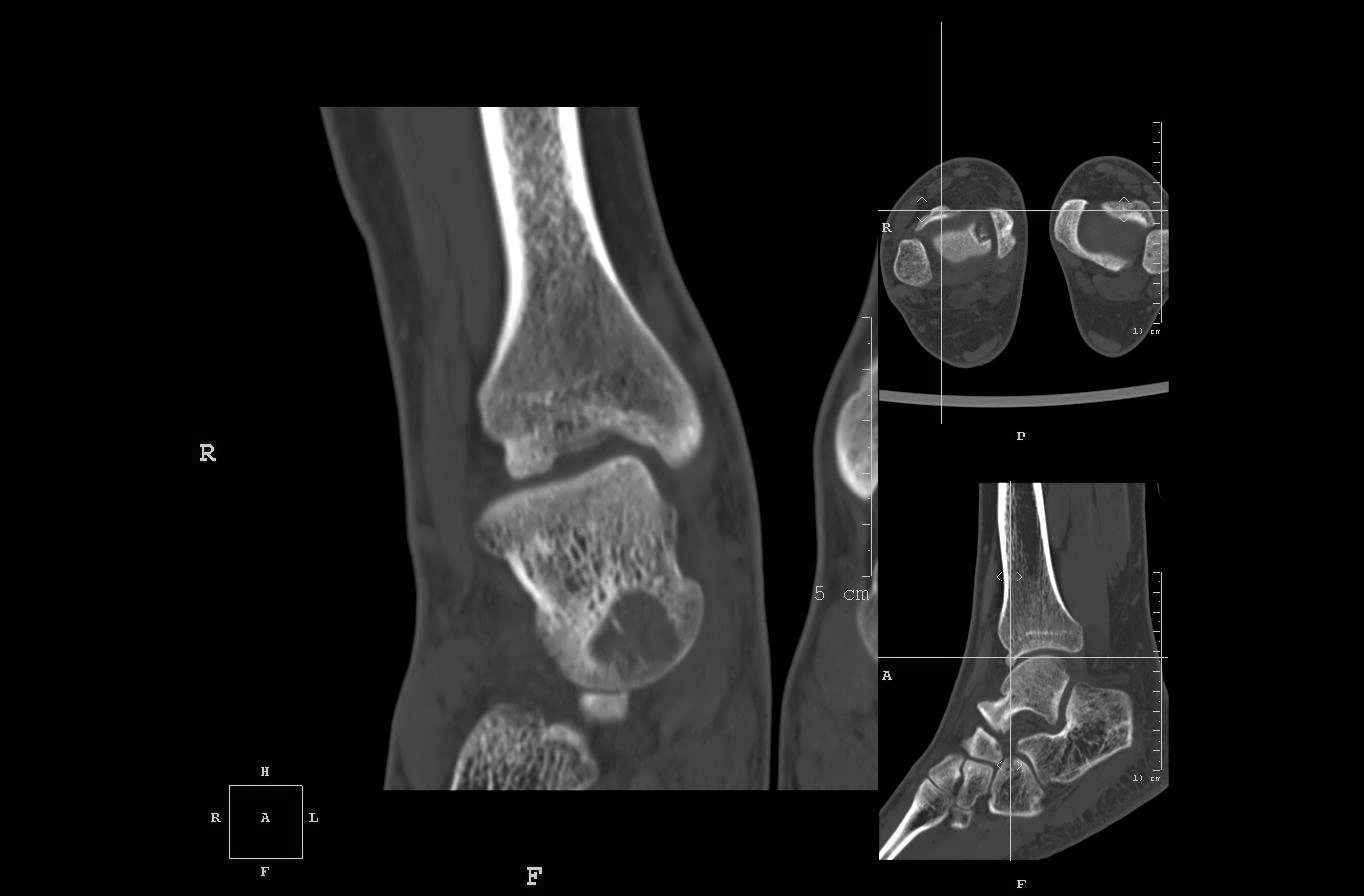

Уважаемые коллеги, обратился за помощью пациент, мужчина, 25 лет. С жалобами на болевой

синдром в области голеностопного сустава и среднем отделе стопы. Травму отрицает. Со слов,

болевой синдром в течении 1 года. Последние 1-1.5 мес периодически вынужден пользоваться

костылями. После ограничения нагрузки боли уменьшаются. Соматически здоров. До появления

болей активно занимался рукопашным боем.

На СКТ картина рассекающего остеохондрита блока

таранной кости, киста шейки таранной кости с признаками импрессии суставной поверхности. А

также - разрастания переднего края б\берцовой кости сопровождающиеся клиникой импиджмент

синдрома.